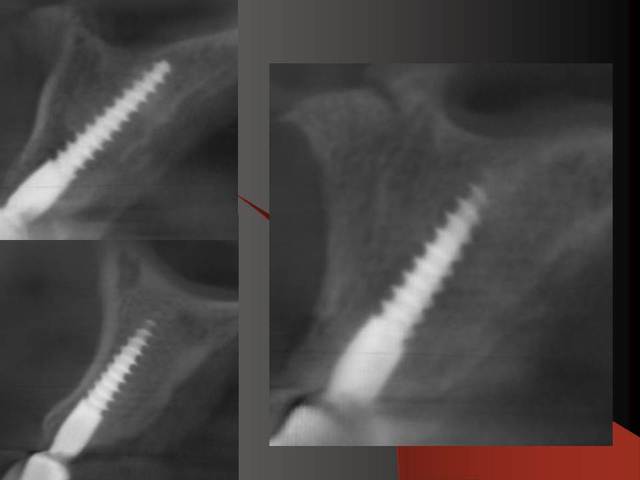

En dessous il y a des photos, dans une on voit (troisième) qu il n y a pas de resorption de l´os après 14 ans, ce que l´on voit c´est l´os très fin condensé sur l´implant.

Le premier photo c´est une erreur parce que le périoste est blessé et les foret "trop" grands.